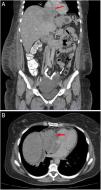

A: Coronal thoracic computed tomography showing left complex adnexal mass (white arrow) and lobulated hepatic mass with compression and displacement of inferior vena cava and right atrial extension (red arrow). B: Axial thoracic computed tomography showing mass with right atrial extension (red arrow).